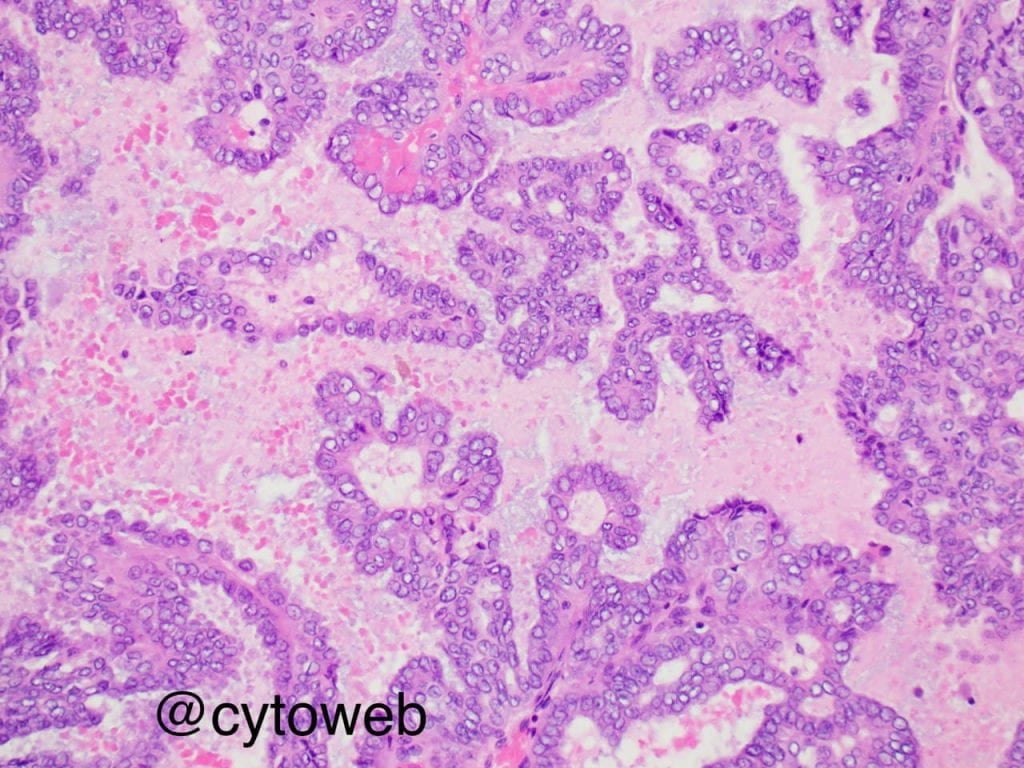

Secretory carcinoma

The salient, but non-specific, cytomorphologic features of secretory carcinoma include the presence of epithelioid cells arranged in sheets, clusters, papillae and as single dispersed cells. The nuclear features are low grade, characterized by mild nuclear enlarged, membrane irregularity and small nucleoli. Identifying the presence of moderate to abundant cytoplasm with multivacuolation may be a helpful clue. These cells may also have an oncocytoid appearance. Another clue is the presence of mucoid or proteinaceous material in the background.